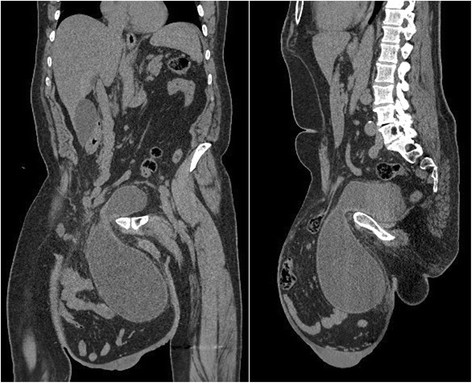

แต่ผล CT Scan แสดงให้เห็นว่า เนื้องอกขนาดใหญ่ราว 30 เซนติเมตรนี้ แท้จริงแล้วคืออาการจากโรคไส้เลื่อนที่ขาหนีบ ซึ่งเกิดขึ้นหลังจากลำไส้เล็กของคนไข้ได้เคลื่อนตัวออกจากบริเวณอุ้งเชิงกราน จนทำให้ลูกอัณฑะของเขาถูกกดทับและบวมเป่งจากภายใน

โดยในรายงานระบุว่า คณะแพทย์ได้ผ่าตัดเปิดผิวหนังออกมา และพบว่าภายในถุงอัณฑะที่บวมเป่งนั้นมีทั้งลำไส้เล็ก บางส่วนของลำไส้ใหญ่ และของเสียอีกจำนวนหนึ่ง

ภาพจาก Journal Case Reports